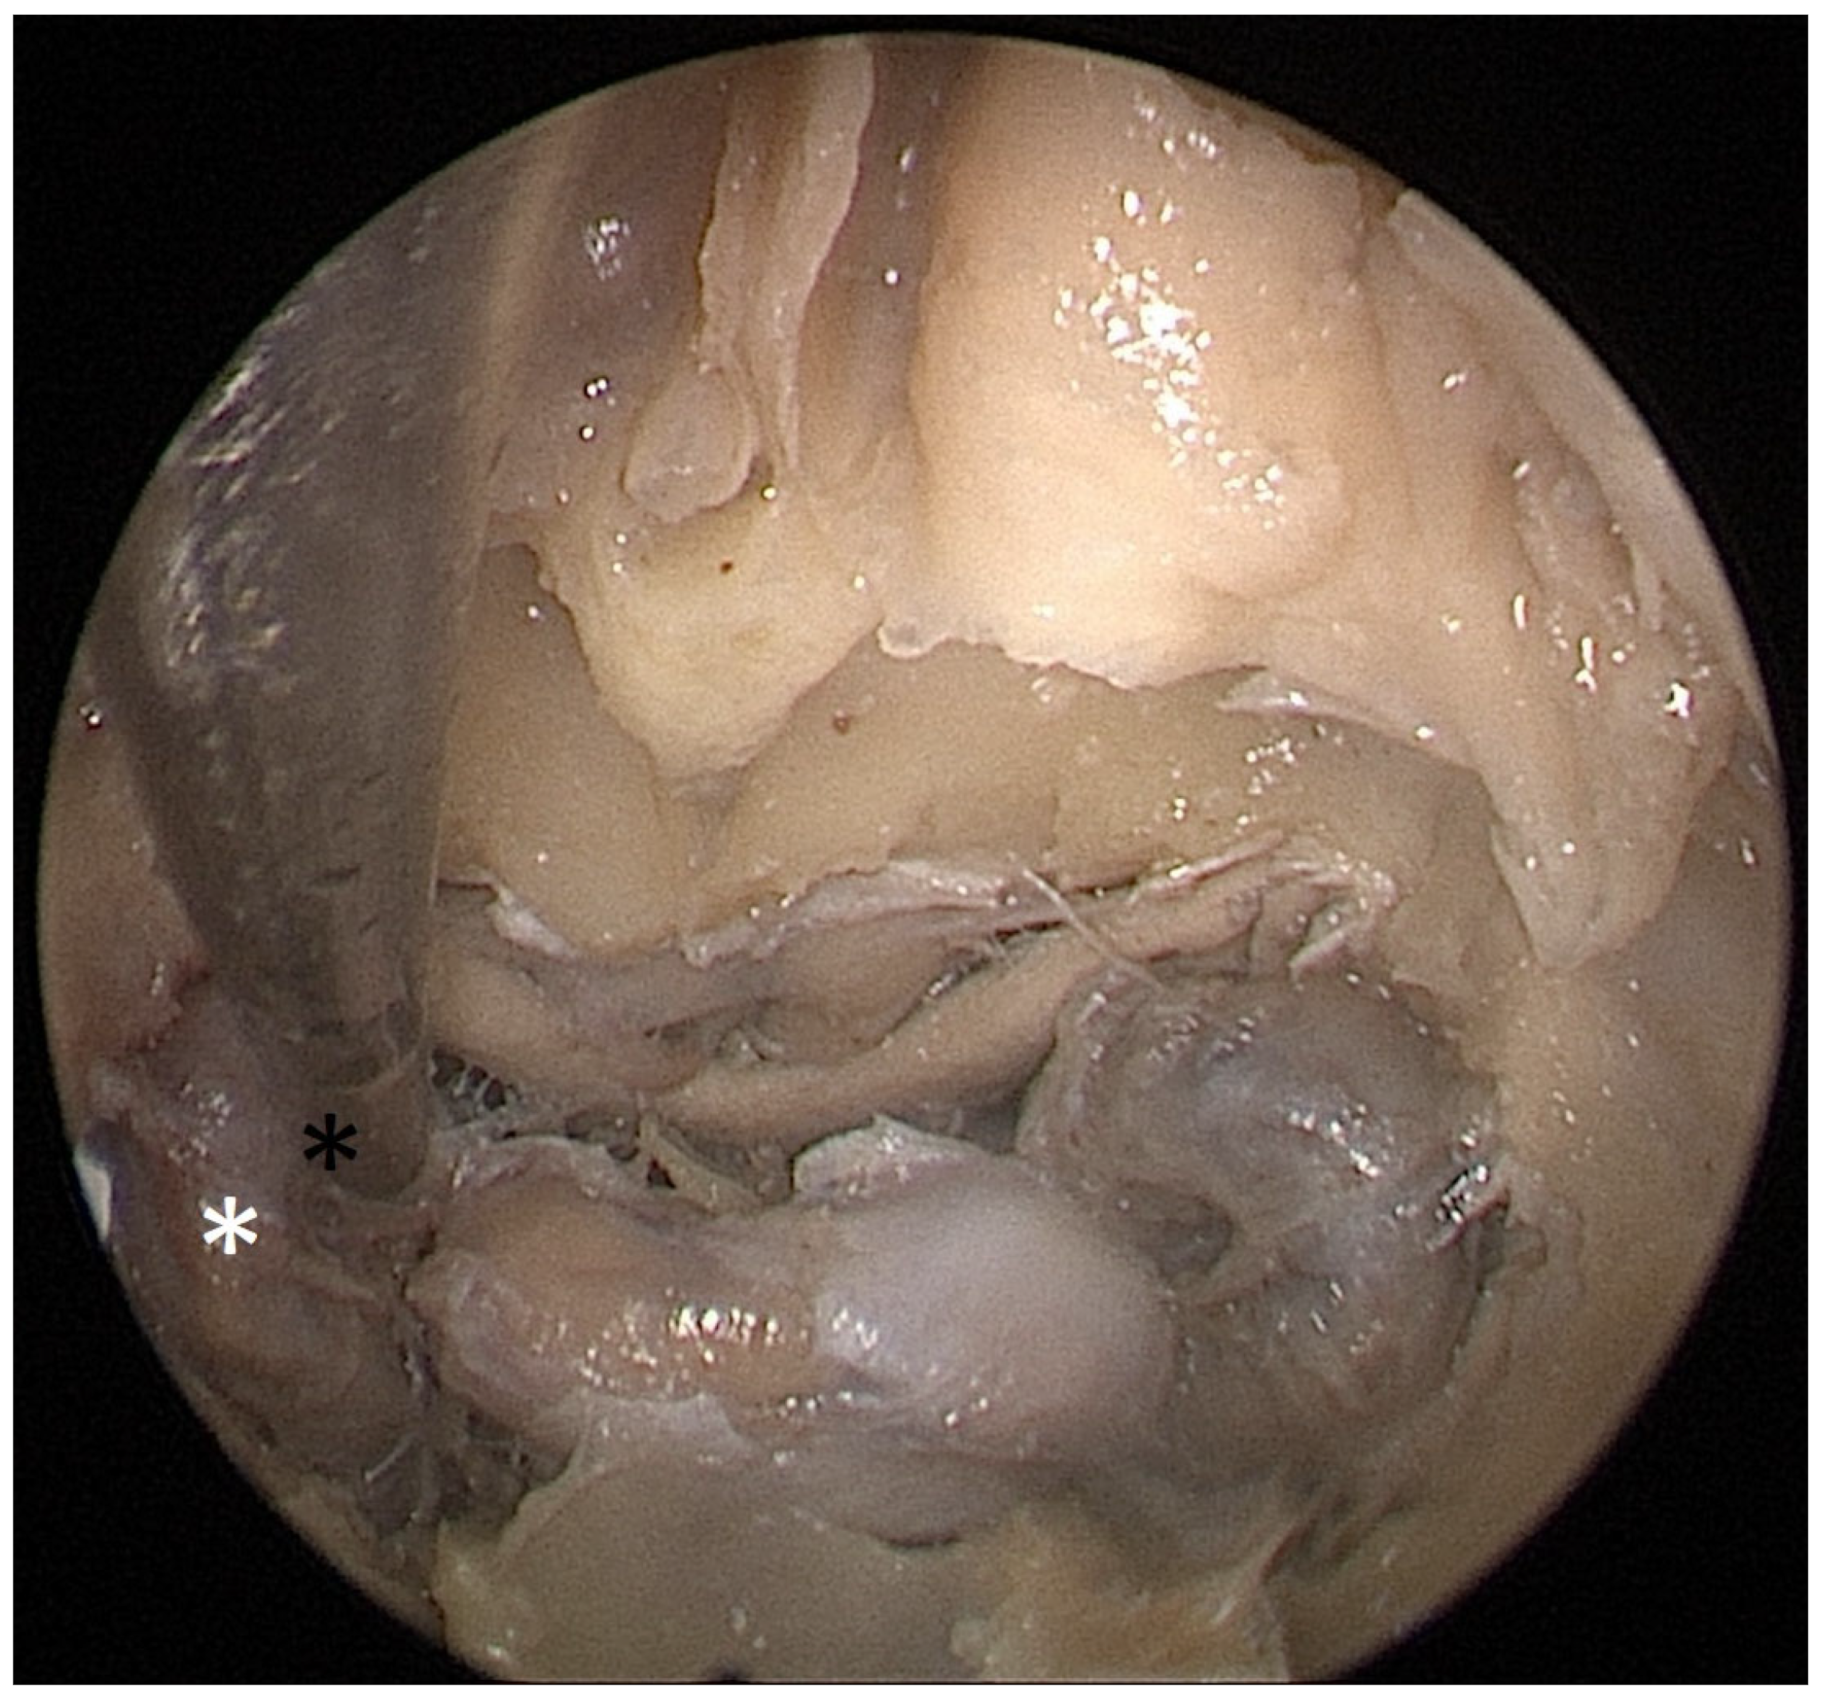

Cadaver pituitary surgery: On each of the two cadaveric heads, we used the paraseptal binostril approach for the sphenoid sinus. A 30° Storz endoscope (Karl-Storz, Austria, Vienna) was used. The head was mounted in a Mayfield cranial stabilization device. The surgery started with a lateralization of the inferior and medial turbinates. The anterior sphenoid wall and ostium to sphenoid sinus were identified. Using the straight suction with a marked scale, 1 cm and 2 cm distances from the anterior sphenoid wall were measured and marked with a scalpel on the posterior part of the septum. Using a scalpel, Kerrison punch, and backbiter punch, a posterior septal resection 1 cm from the anterior wall of the sphenoid was performed. We continued with the wide opening of the sphenoid cavity and resection of the intersphenoidal septum and the full exposure of the posterior wall, both ICAs, and optocarotic recesses (OCR). The posterior wall of the sphenoid sinus and dura were resected to better identify anatomic landmarks, with both ICAs, pituitary gland, chiasma, and optic nerves visible at the end of a resection (Figure 4). The straight suction was inserted into the sphenoid sinus so that the instrument’s tip was in the most lateral position in the sphenoid sinus without infracturing the rest of the nasal septum. A picture was taken in this position to evaluate the most lateral part of the sphenoid sinus that could be reached with a straight instrument with a 1 cm septal resection without infracturing the nasal septum (Figure 5). Enlargement of the septal resection to 2 cm from the anterior sphenoid wall was performed with a backbiter punch and scalpel. The straight suction was inserted into the sphenoid sinus so that the instrument’s tip was in the most lateral position in the sphenoid sinus without infracturing the rest of the nasal septum. A picture was taken in this position to evaluate the most lateral part of the sphenoid sinus that could be reached with a straight instrument, with a 2 cm septal resection, without infracturing the nasal septum (Figure 6).

Figure 4. Opened sphenoidal sinus, endoscopic view, fully exposed ICAs (white asterisks), pituitary gland (black and white star), and optical chiasm (black arrow).